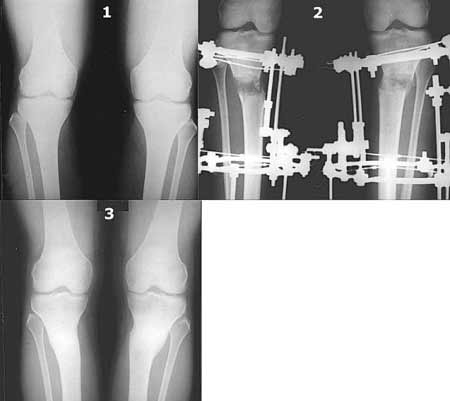

Года 2-3 назад эта тема возникла в англоязычном Ортоподе. Даже я напрягся - дискутировал на ангельском языке, отправлял картинки.

Картинки - в приложении.Будут вопросы - готов ответить.

Ещё картинка - схема. Хотя у Соломина всё написано.

Вот ещё картинки, которые отправлял в Ортопод. Коррекция кривизны и удлинение на 3 см.